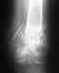

Добрый день, 5.10.2011 упав с высоты сломал ногу, диагноз таков: двухлодыжечный перелом левой голени с подвывихом кнаружи.

Добрый день, 5.10.2011 упав с высоты сломал ногу, диагноз таков: двухлодыжечный перелом левой голени с подвывихом кнаружи. Сложили отломки.Наложили гипсовый сапожок сделали снимки, положили в стационар, врач сказал если не будет рецидива подвывиха, то отпустить домой. Сегодня 10.10.11, домой не отпустили из гипса сделали лангету, пришел врач и еще 5 человек, я так понял это консилиум. Сказал, что из ха подвывиха обломки, как я понял не сопоставить, что нужен синтез лодыжек, нужна отперация, титановая пластина с болтами. Дал время подумать. Я то в этом ничего не смыслю, поэтому хотелось бы для принятия решения независимой консультации в УНИИТ, и возможно ли у вас сделать такую операцию если уж без нее никак? Спасибо!